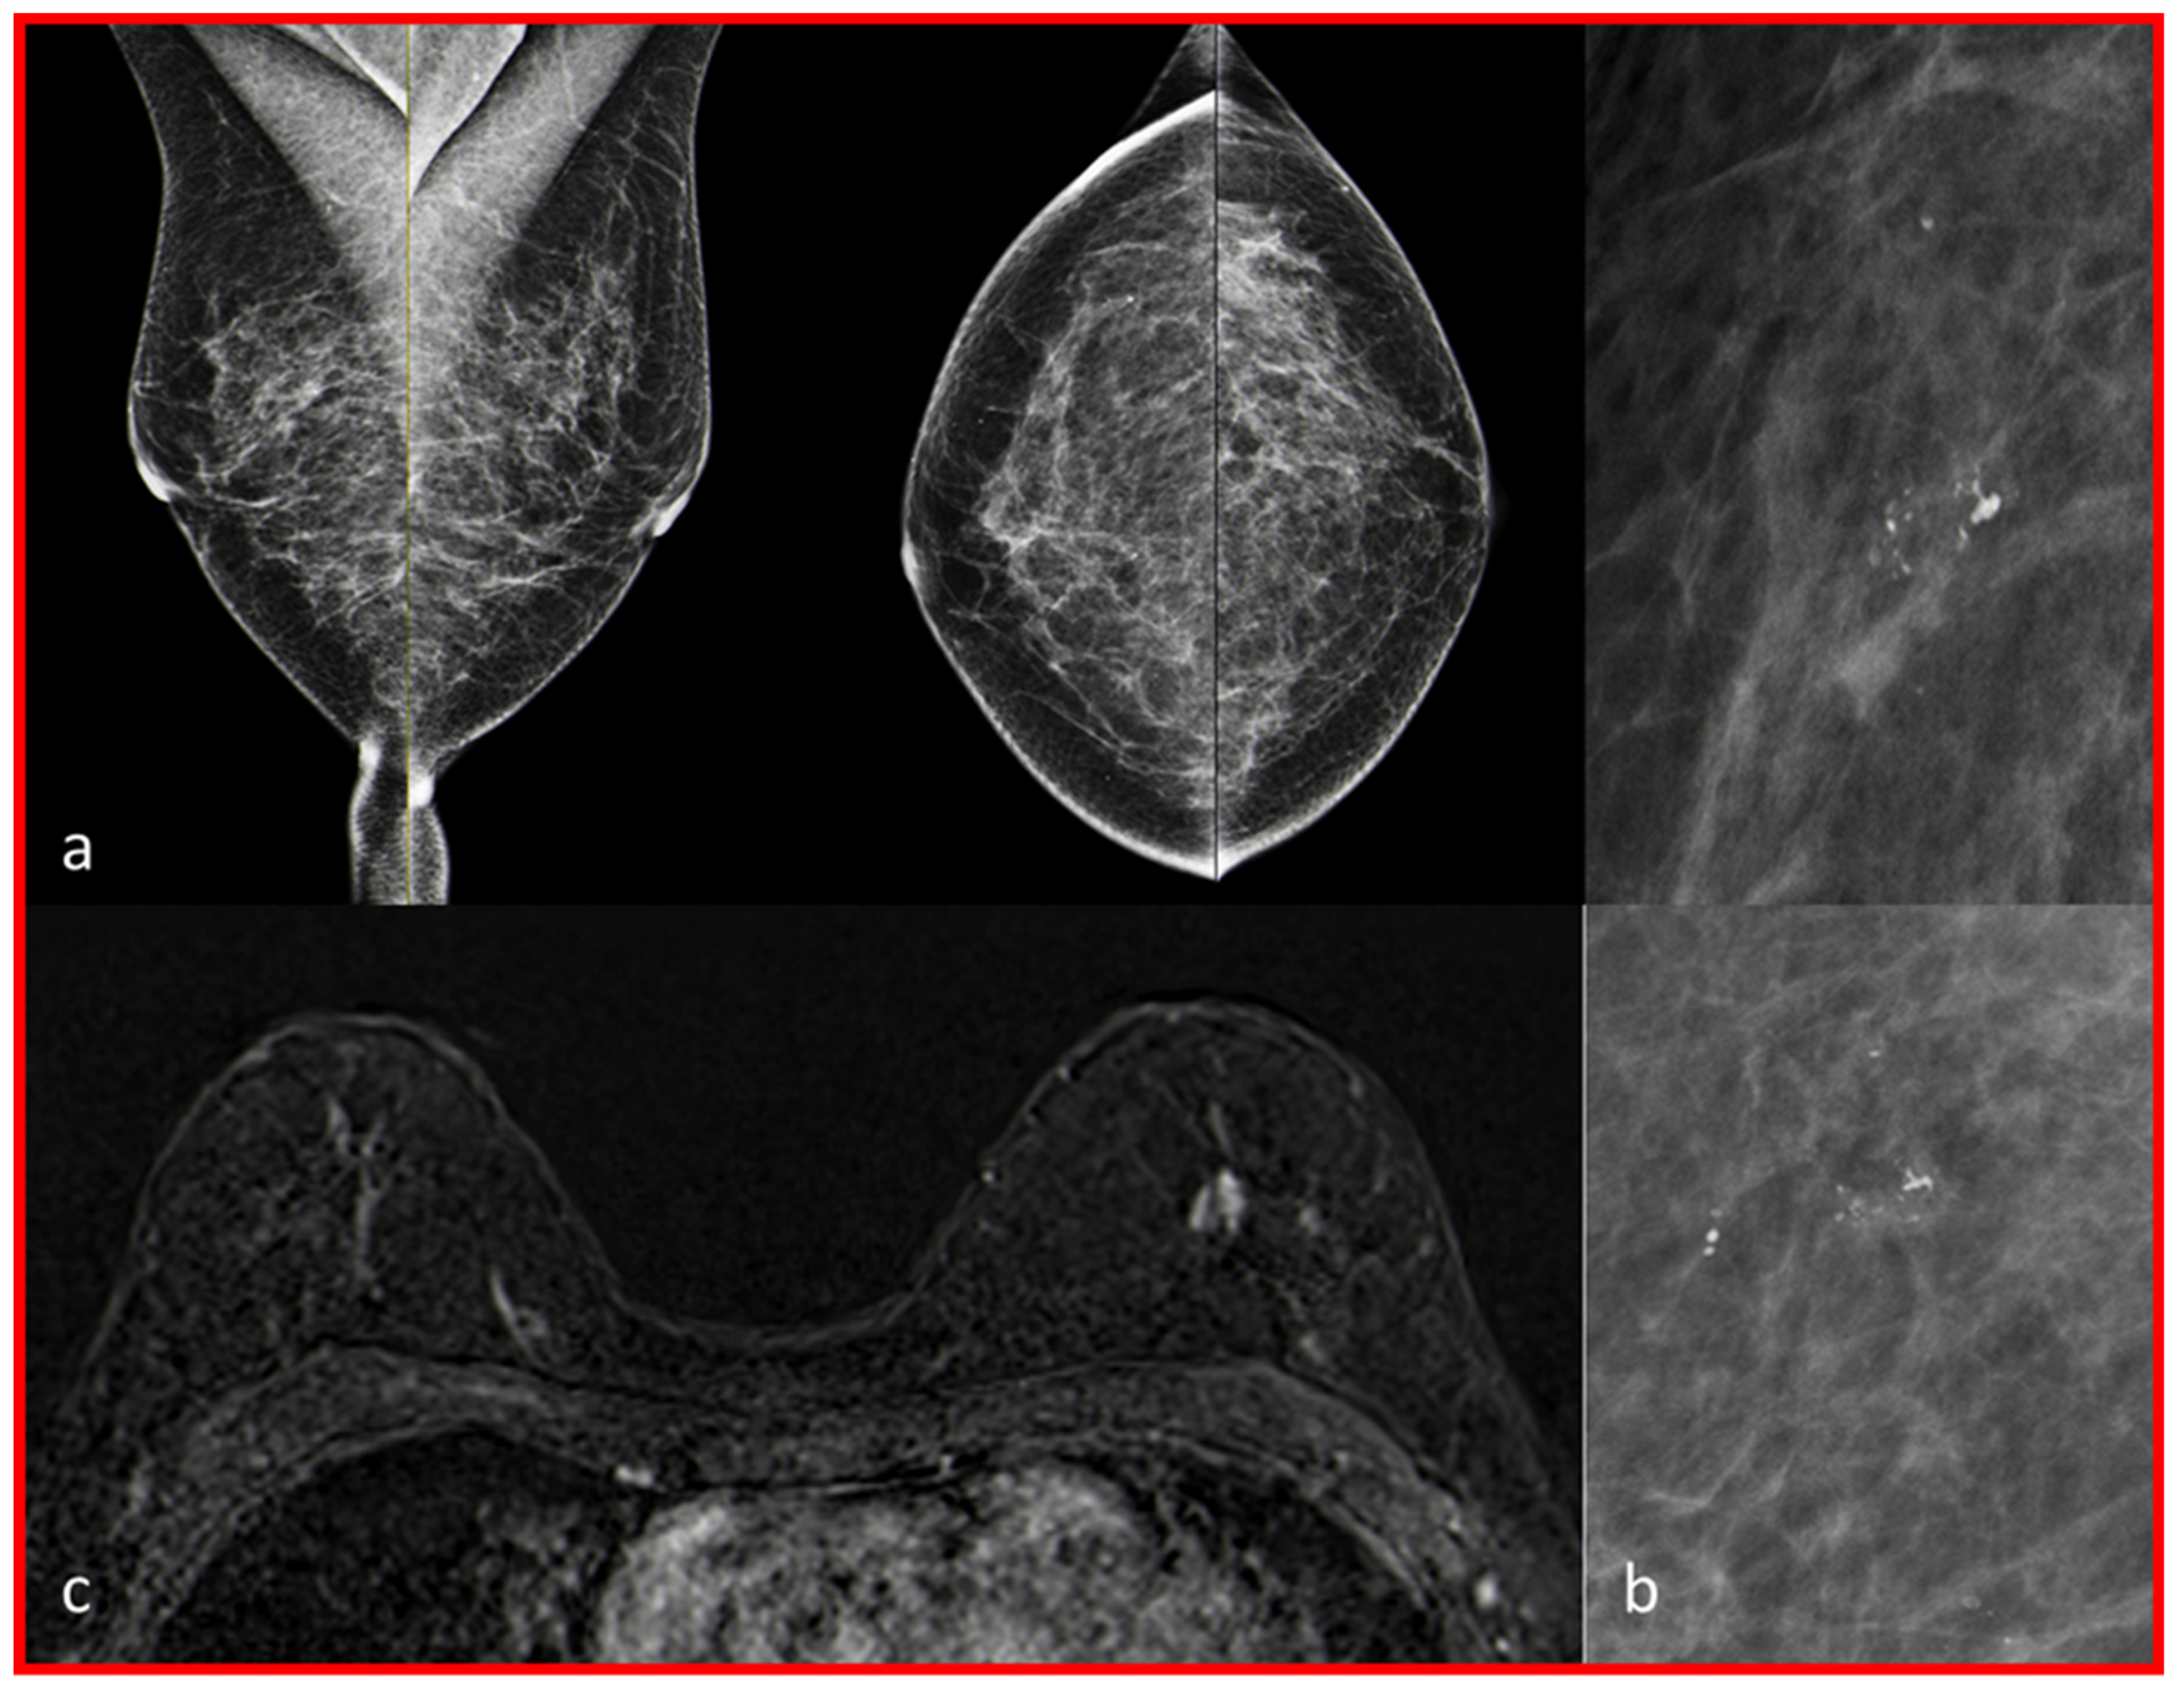

| 2 | 1 | Marked | C | Low-grade DCIS (0.15 cm) | No contrast enhancement in the position of macrocalcifications. |

| 3 | 1 | Marked | C | Low-grade DCIS (5.6 cm) | No contrast enhancement in the position of macrocalcifications, multiple cysts on both sides. |